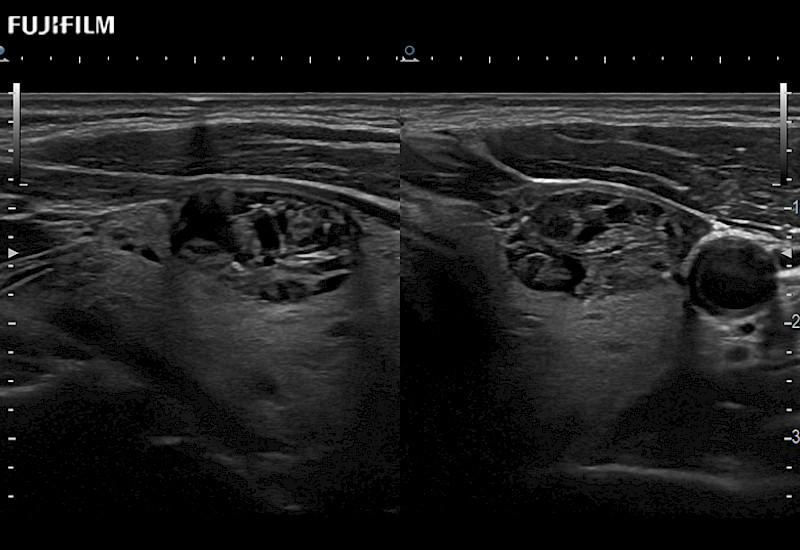

Extraordinary high-resolution digital imaging

Our dedication to Surgical Oncology allows us to offer superior image quality, outstanding system reliability and intuitive use of cutting edge technology.

- Instant feedback on tumor margin delineation

- Valuable information to guide tumor resections

- Flat array geometry combined with trapezoid imaging results in less surface pressure on organs while providing a very wide field of view

- Instant feedback on tumor margin delineation